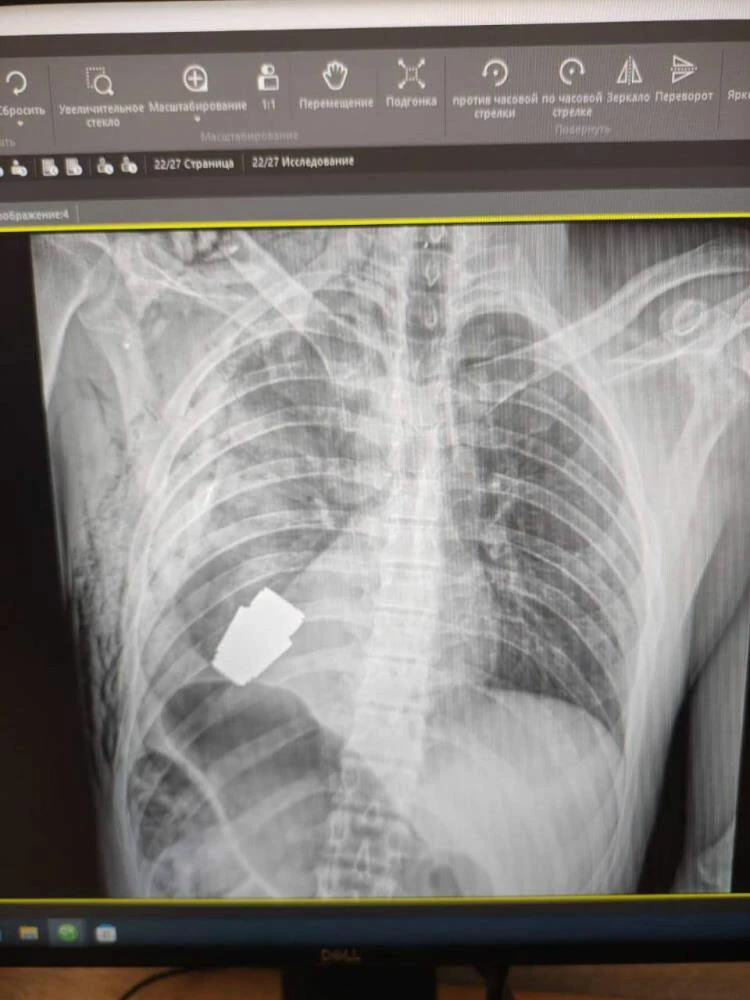

Rusya Devlet Başkanı Vladimir Putin'in 24 Şubat'ta verdiği askeri emirle başlayan Ukrayna'nın işgali yaklaşık bir senedir şiddetli çatışmalarla devam ediyor. İşgal boyunca enerji altyapısı Rus füzeleriyle harap edilen Ukrayna'da zorlu şartlar altında birçok ameliyat gerçekleştirildi. Son ameliyat ise Ukraynalı bir askerin kalbine yakın bölgesinden patlamamış VOG el bombasının çıkarılması oldu.

Bombanın her an patlayabilme ihtimali olduğu için Ukrayna Silahlı Kuvvetlerinin en deneyimli cerrahlarından biri olan Andrii Verba tarafından acil bir operasyon gerçekleştirildi. Ukrayna Savunma Bakanı Yardımcısı Hanna Maliar, cerrahi müdahalenin başarılı olduğunu ve askerin tedavi altına alındığını söyledi.

El bombasının askerin vücuduna nasıl girdiğine dair ise açıklama yapılmadı.